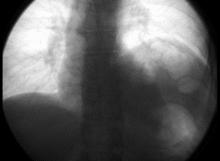

Left phrenic nerve palsy (right image side) in fluoroscopy: forced inspiration with closed mouth leads to paradox elevation of the paralytic left diaphragm while the healthy right side moves down.

The phrenic nerve must be identified during thoracic surgery and preserved. To confirm the identity of the phrenic nerve, a doctor may gently manipulate it to elicit a dartle (diaphragmatic startle) response.[7] The right phrenic nerve may be crushed by the vena cava clamp during liver transplantation.[8] Severing the phrenic nerve, or a phrenectomy,[9] will paralyse that half of the diaphragm. Bilateral diaphragmatic paralysis or BDP can also be caused by spinal cord injury, motor neuron disease, infection, pneumonia, sarcoidosis, multiple sclerosis, polyneuropathy, myopathy and amyotrophy, cardiac surgery, lung transplantation, or mediastinal tumors.[10][11] Diaphragm paralysis is best demonstrated by sonography.[8] Breathing will be made more difficult but will continue provided the other nerve is intact.